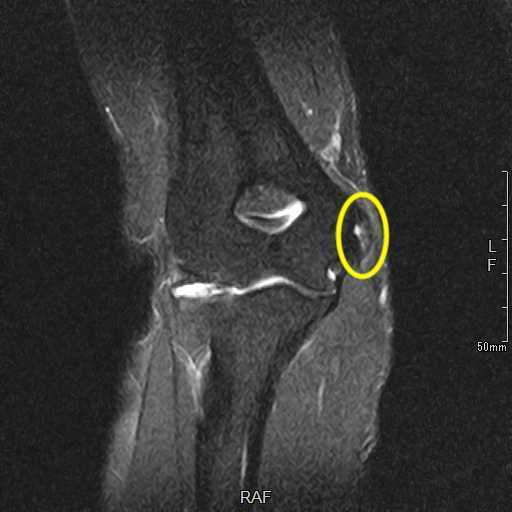

肘の離断性骨軟骨炎(以下:OCD:osteochondritis dissecans)は上腕骨小頭という部位に好発することが多いです。

OCDは成長期の代表的なスポーツ障害であり、野球などといった投球・投擲動作を行うスポーツ選手で投球側に発生することが多いです。大半は10-12歳で発症し成長期における有病率は2-3%と頻度は少ないが進行するとスポーツにみならず、日常生活お支障をきたすことが多い怪我です。そのため、早期発見・早期治療が重要となります。

OCDを発見するにはレントゲンや超音波検査で上腕骨小頭軟骨下骨の状態を観察します。

軟骨下骨の不整像が軽微か不明の場合はMRI検査を行いOCDの確定診断を行います。

症例提示

12歳・男性・スポーツは野球(週2回/4年間)

2024年3月頃から外傷誘因なく疼痛出現。

2024年4月上旬、他院受診して超音波検査で軟骨が剝がれていると診断を受けたが経過観察のみ。

2024年5月、当院受診。レントゲン撮影をして離断性骨軟骨炎と診断されてリハビリ開始。

リハビリでは、徒手療法(マッサージ)・運動療法(筋力トレーニング ストレッチ)・物理療法を実施していましたが、

疼痛消失には至らず、組織修復を目的に体外衝撃波を実施しました。

体外衝撃波(拡散型圧力波治療)は、週1回の頻度で3回実施しました。

現在は、リハビリテーションでトレーニング継続中です。